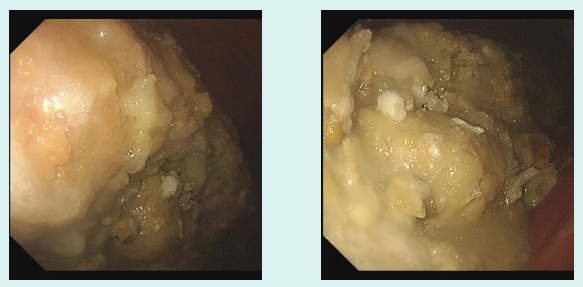

接诊的吕主任详细询问病史后,初步判断关女士可能因大量食用山楂引发了胃结石。随后的无痛胃镜检查证实了这一猜测——关女士的胃体里有一颗超大结石。

由于结石体积过大,无法直接通过内镜取出,吕主任建议她回家后通过饮用碳酸饮料配合药物治疗,尝试溶解结石。